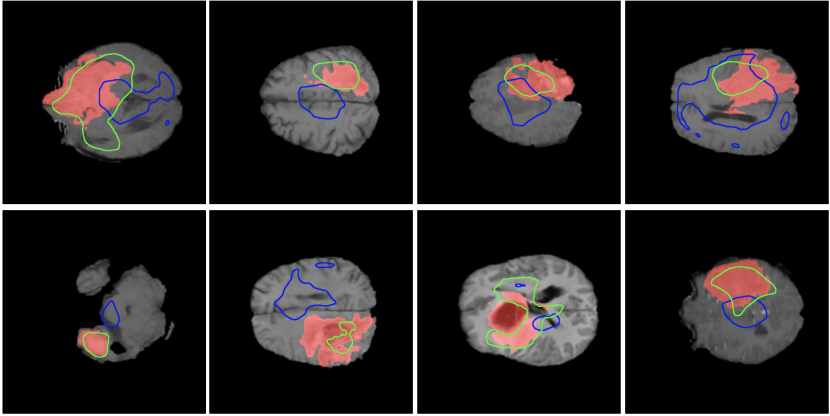

Results on BRATS. In Table IV, we present the brain lesion detection and localization results obtained by the anomaly detection models [56, 57, 61] on BRATS, before and after adding SSPCAB and SSMCTB, respectively. Remarkably, we notice that the results of DRAEM, NSA and FastViT+NSA show significant performance improvements when integrating SSMCTB. Moreover, the performance gain brought by SSMCTB is always higher than the gain brought by SSPCAB. When taking advantage of the 3D nature of the MRI scans by employing the 3D SSMCTB, we attain even higher performance with DRAEM.

BRATS. BRATS [63] is a multimodal magnetic resonance imaging (MRI) data set for brain tumor segmentation. It is an intrinsically heterogeneous data set that contains brain tumors of different shape, appearance and histology. The data set comprises manually annotated MRI scans acquired by 19 institutions employing different clinical protocols. To evaluate anomaly detection models, we introduce a novel split of the data set, such that all training images are lesion-free, i.e. all images with lesions are kept for testing. The training set includes 11,280 slices (125 scans), which leaves 27,745 slices (180 scans) for the test set.